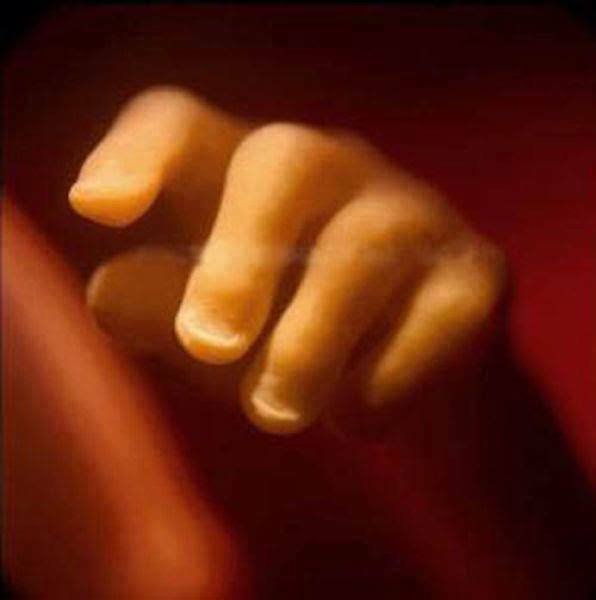

18. 懷孕18週,我們可以明顯看到胎兒的指甲。(看到小手手就瞬間融化了...)

19. 到了第20周,胎兒差不多有20公分長,而且頭上也長出了胎毛。